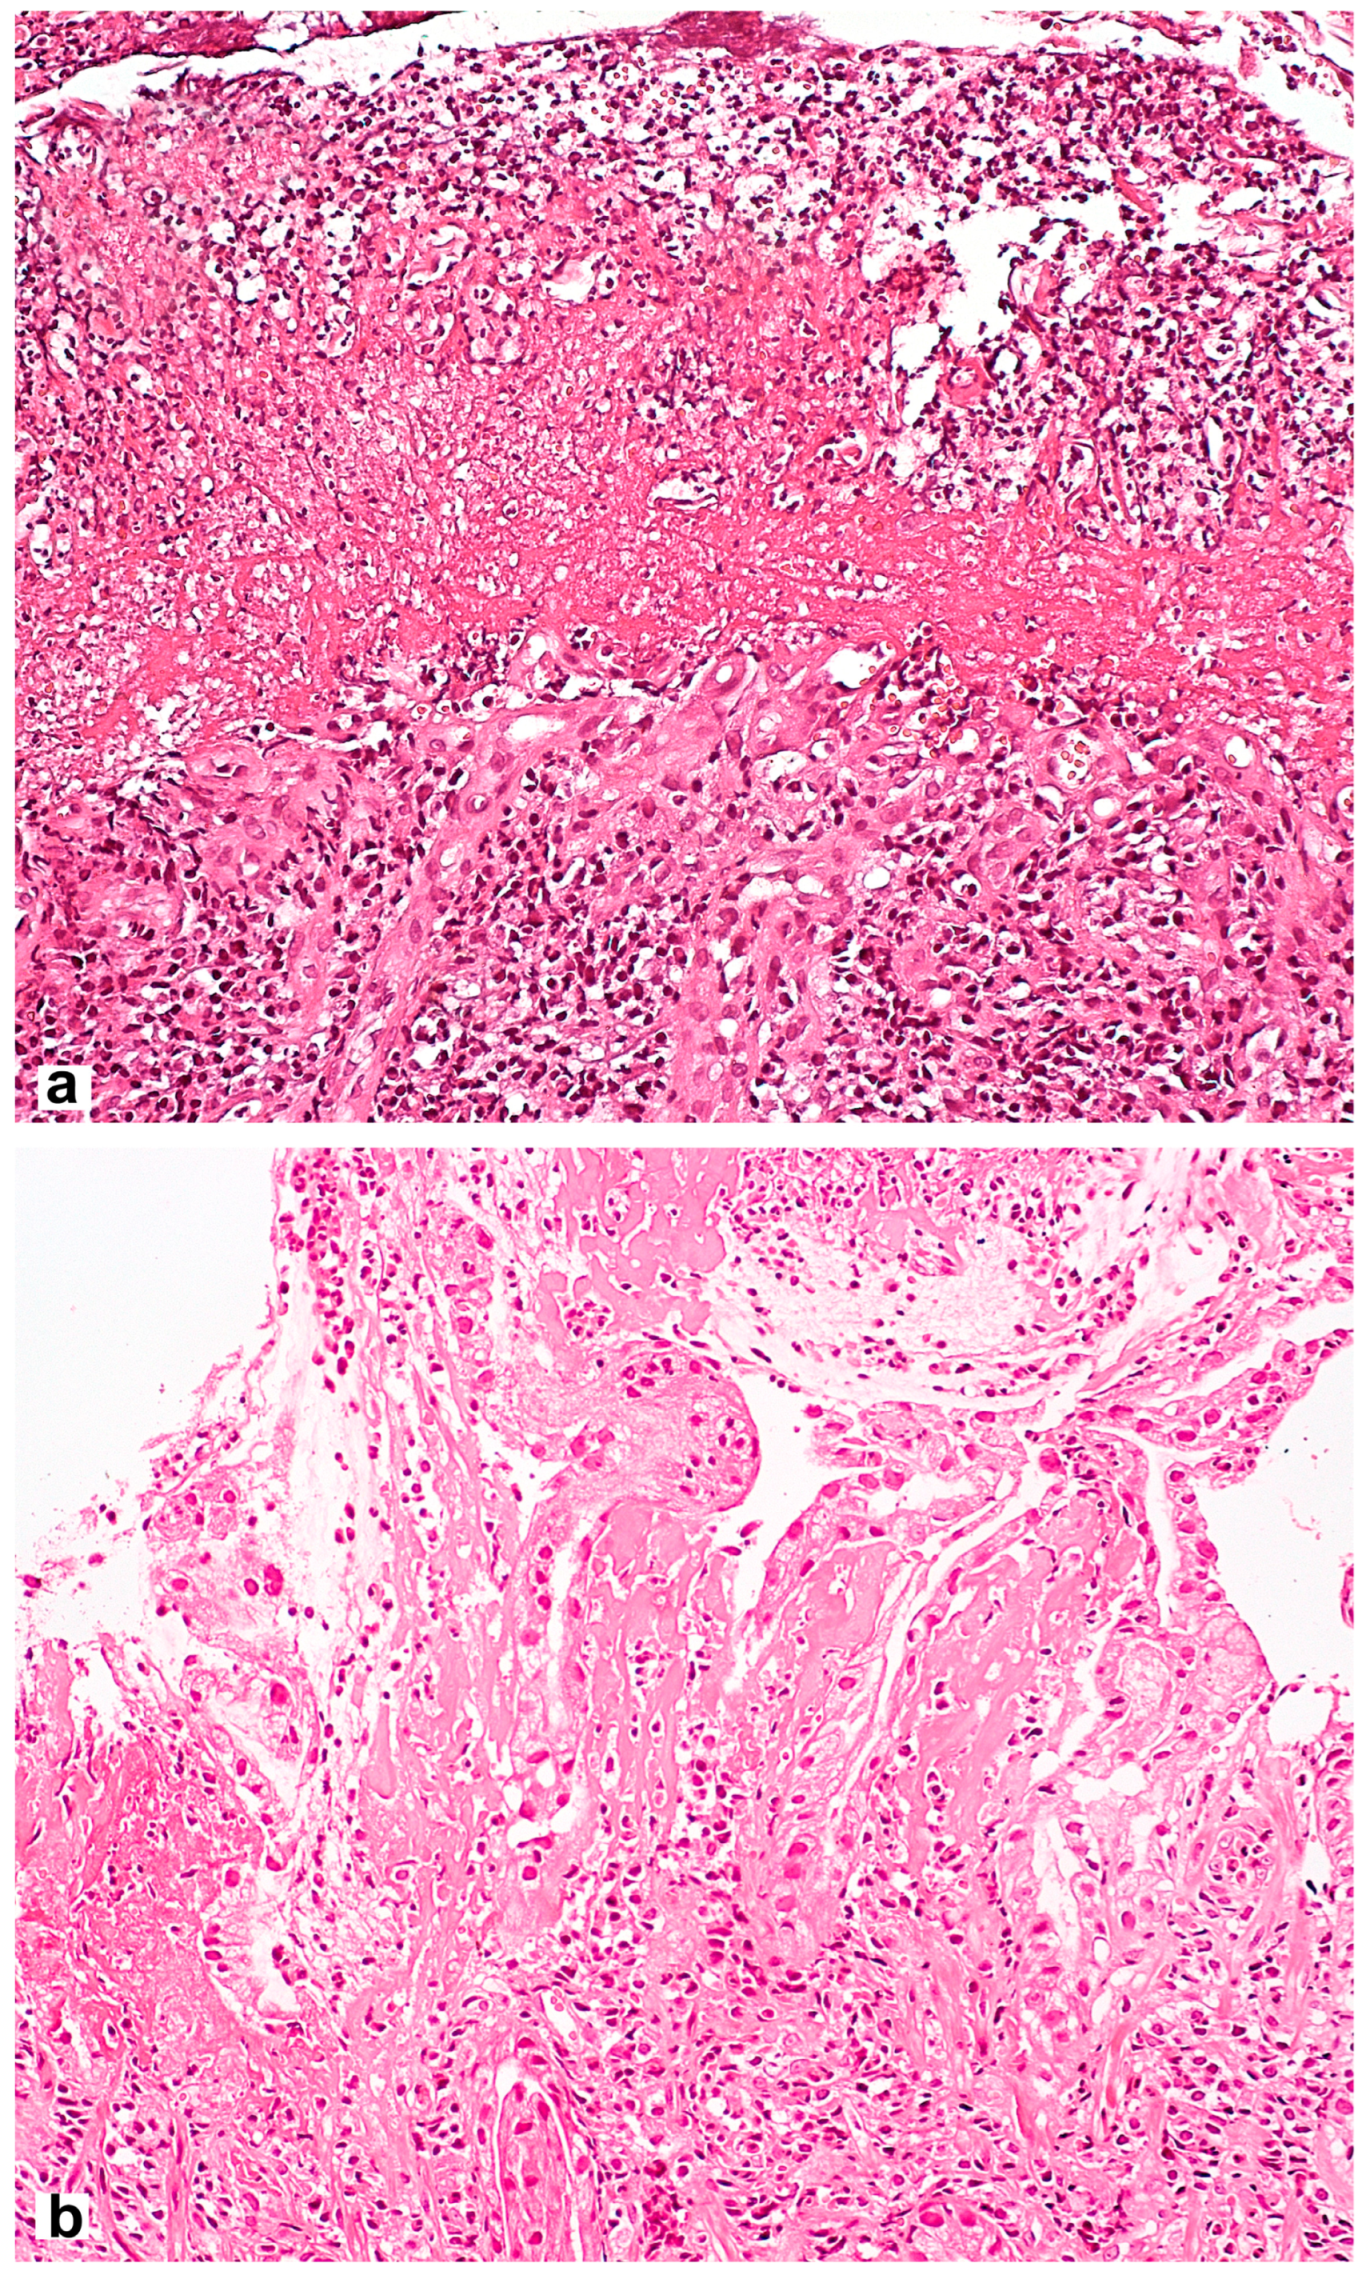

Microscopic signs comprise the picture of the so-called reactive gastropathy, which is not strictly specific to NSAIDs. There is a weak–diffuse, predominantly mononuclear inflammatory infiltration of the lamina propria, often revealing erosive and/or ulcerative defects, pronounced regenerative changes in the epithelium (foveolar hyperplasia with hyperchromic cell nuclei, decreased mucus formation), mucosal edema with vascular ectasia in the lamina propria and lamina propria expansion with fibromuscular proliferation. Subnuclear vacuolated mucous cells may be an additional criterion, which is associated with operated stomach syndrome. Interestingly, the nature of the necrotic masses at the bottom of the defect may be the starting point for the differential diagnosis between NSAID-associated lesions with a homogeneous eosinophilic zone of necrotic masses and a defect caused by Helicobacter pylori (H. pylori) [28] with the presence of necrotic masses that are loosely associated with the lamina propria, with immured fragments, necrotic cells and neutrophilic leukocytes (Figure 2). NSAID exposure, in very rare cases, is accompanied by the formation of diaphragms (diaphragm disease) in the stomach. This phenomenon is more typical of damage to the small and large intestines.

Figure 2.

Differential diagnosis between NSAID-associated lesions and a defect caused by Helicobacter pylori. (a) Helicobacter pylori-associated gastric erosion. Inhomogeneous masses of fibrinoid necrosis with cell debris and granulocytes. (b) NSAID-associated gastric erosion. Homogeneous eosinophilic ischemic necrosis blending into the adjacent lamina propria. Hematoxylin and eosin stain ×200.